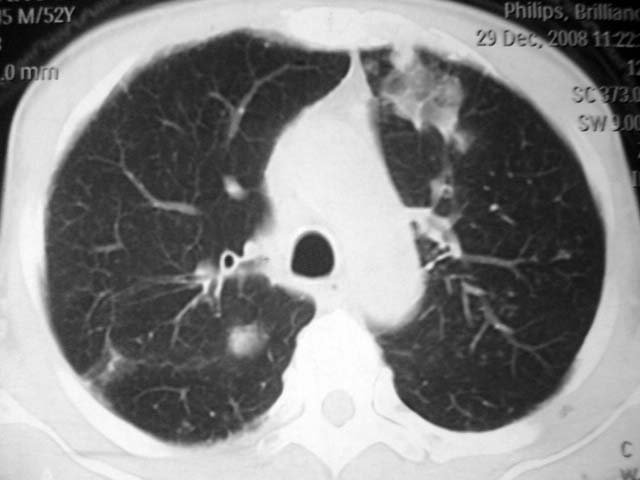

男,52岁,发热2月,糖尿病史。

抗结核治疗irpz方案,血糖未治疗,空腹15.9左右。症状无好转,左胸痛。

2、双肺见多发片状及结节状高密度影,大多数病灶中心均见“空泡征”。

3、纵隔内淋巴结肿大。

结果:两肺继发性肺结核并曲霉菌感染。